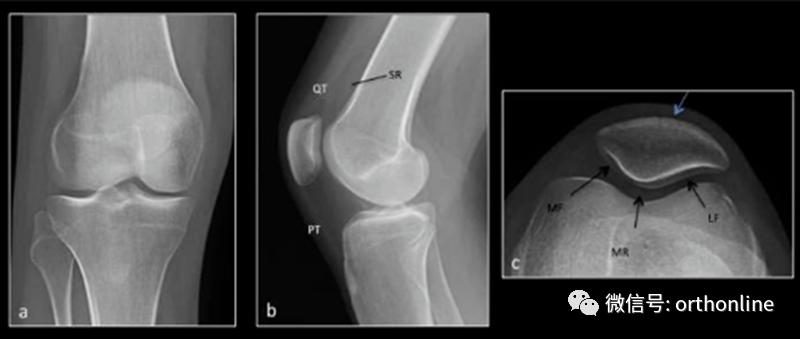

正常X线 a.膝关节正位 b.膝关节侧位 c.髌骨轴位